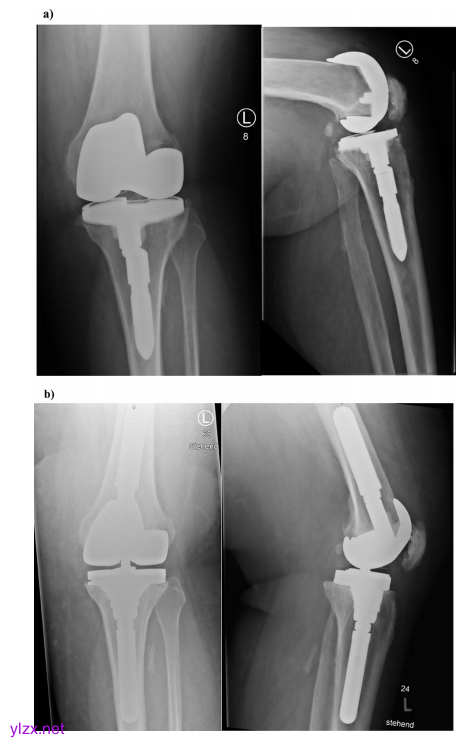

病例2显示,一名52岁的病态肥胖男性患者,患有多向不稳定KDC B和股骨和胫骨组件无菌性松动。a左侧为定性x射线前后视图,右侧为侧视图。带胫骨模块化非骨水泥股骨干的无约束、保肢假体。股骨和胫骨干周围可见射线透亮线。

b术后x射线左前后视图和右侧视图。在单阶段置换中取出植入物后,股骨显示出KDC 1缺陷。PMMA可以增强小骨骺缺损。胫骨组件的移除导致KDC 2缺陷,采用干骺端套筒和非骨水泥模块化股骨干假体进行治疗。由于关节线解剖重建(KDC B)后持续不稳定,选择了旋转铰链假体